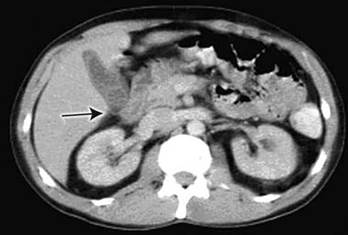

Figure 9 – Computed tomography on admission showed pericholecystic inflammation, suggesting acute cholecystitis, and a possible gallstone